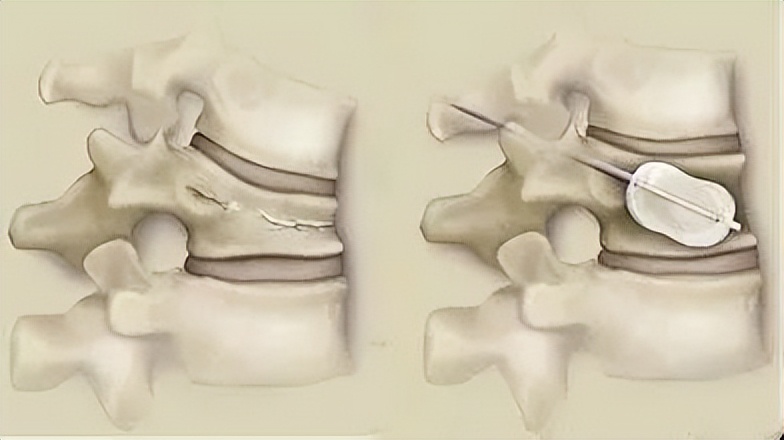

椎体成形术

椎体成形术 ,全称为 经皮穿刺椎体成形术 (PVP),是通过向病变椎体内注入骨水泥,达到强化椎体的技术。还有一种是球囊扩张椎体后凸成形术(PKP),先用球囊扩张然后再注入骨水泥,二者均属于微创手术,都能增加椎体强度和稳定性,防止塌陷,缓解疼痛,甚至部分恢复椎体高度。

手术是在局麻下完成,在背部做一个约2-5mm的小切口,用特殊的穿刺针在X线监护下经皮肤穿刺进入椎体,将骨水泥注入椎体内。手术创伤很小,一般均可耐受。如果实在不能耐受俯卧位,还可采用侧卧位手术。对于高龄体弱的患者而言,采用椎体成形术可极大减少手术风险,且避免了长期卧床所导致的各种潜在并发症。